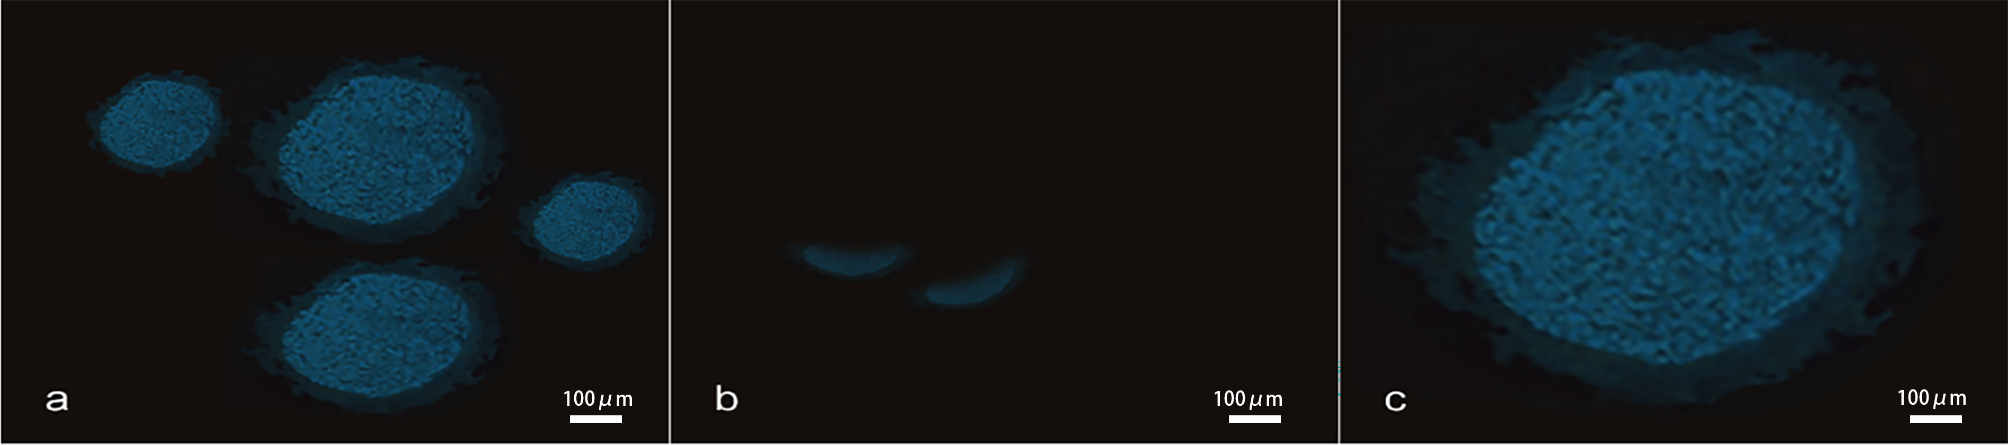

Fig. 4

(a) Fluorescence visualization of CD-Annexin V antibody complex in the main trunk of the femoral nerve, ×200, scare bar, 100 μm; (b) Fluorescence visualization of CD-Annexin V antibody complex in the muscular branch of the femoral nerve, ×200, scare bar, 100 μm; (c) Fluorescence visualization of CD-Annexin V antibody complex in the saphenous nerve, ×200, scare bar, 100 μm.